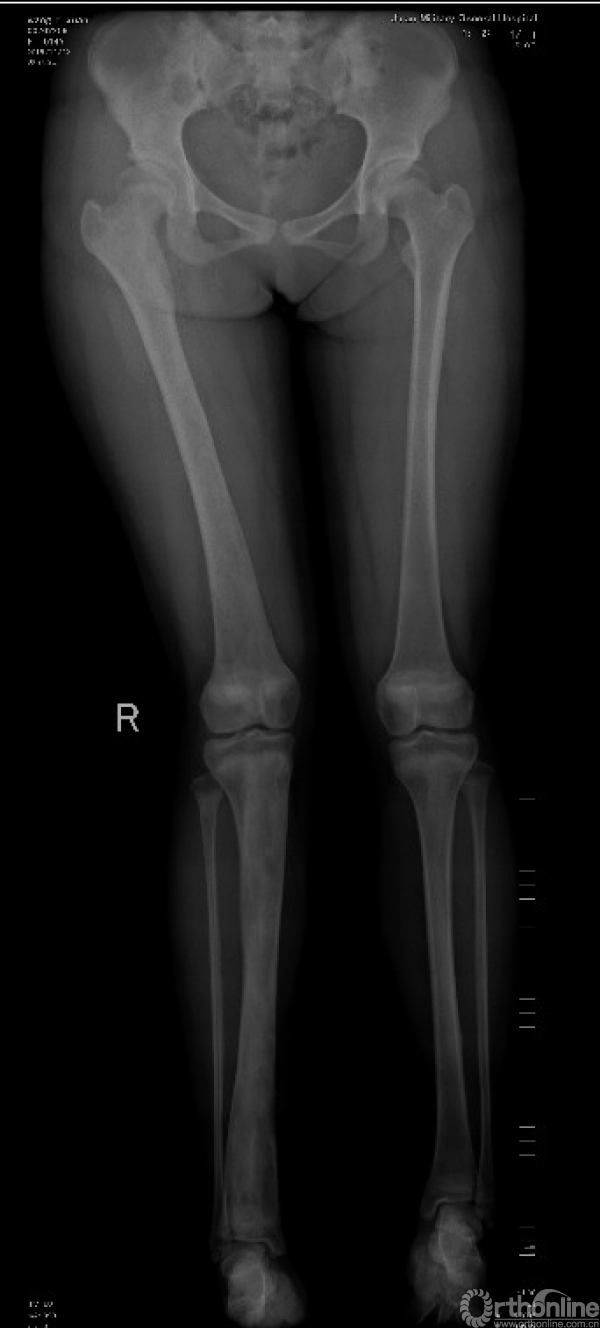

(2)多发型:占骨纤维异样增殖症的30%,病变可侵犯全身多数骨骼,常偏于一侧肢体骨,常以中线为界,严重的可造成肢体短缩(图3),偶尔也有双侧生长(图4)。

图3 右侧骨盆、股骨、胫骨多发病变、畸形